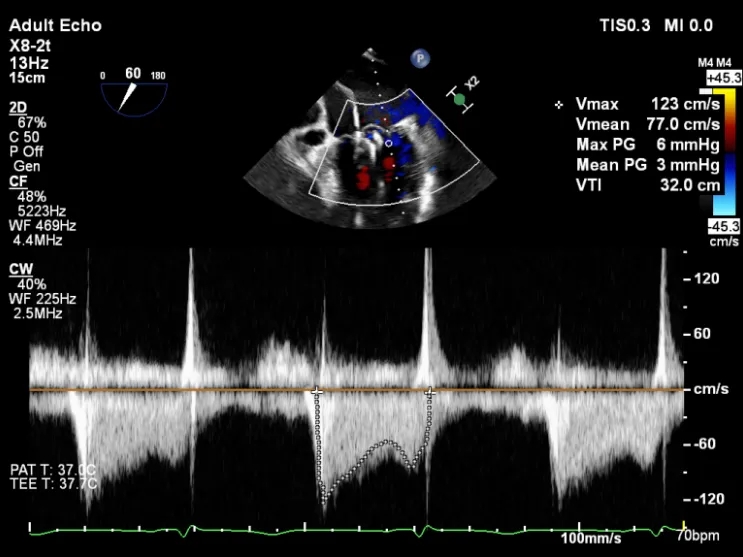

第二枚XTR植入后瓣口平均压差3mmHg

第3枚XTR夹合器植入后,跨瓣平均压差为3mmHg

术后2D TTE:

术后TTE可见二尖瓣微量-轻度反流,三尖瓣反流明显改善降至中度